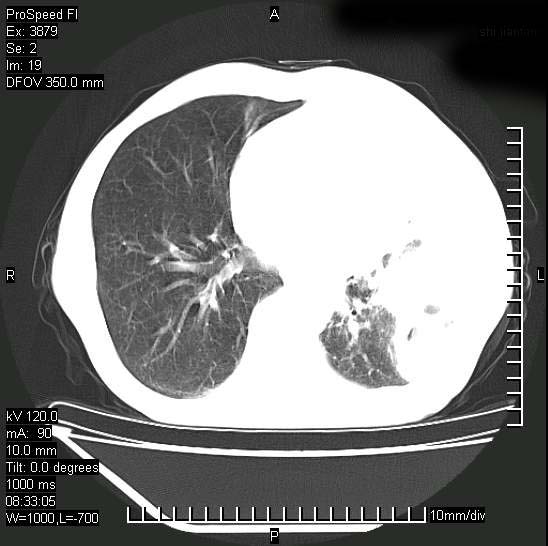

以下是引用37度在2008-6-6 11:20:00的发言:[br]1.包裹性积液,多考虑结核性;[br]2.穿刺术后改变。

以下是引用312nanyang在2008-6-6 15:12:00的发言:[br]基本支持楼主意见[br]疑问?左下肺支气管旁的软组织(16层)密度怎么解释?淋巴结还是斜裂胸膜增厚所致?能否增强进一步检查